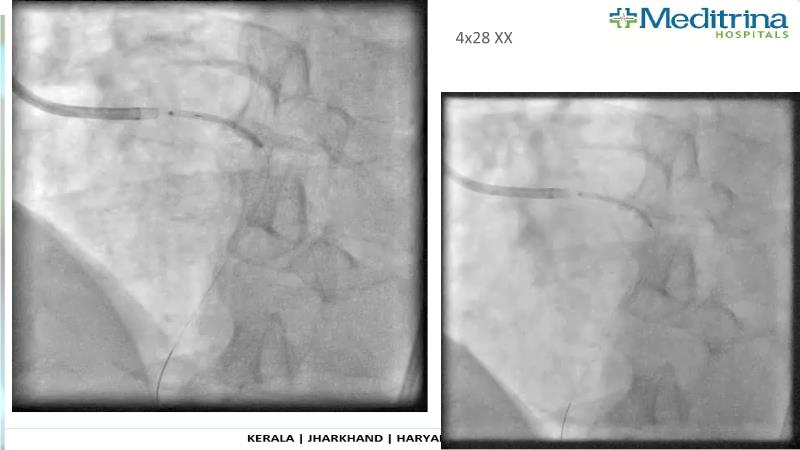

- To define the use of OCT in PCI of complex coronary lesions